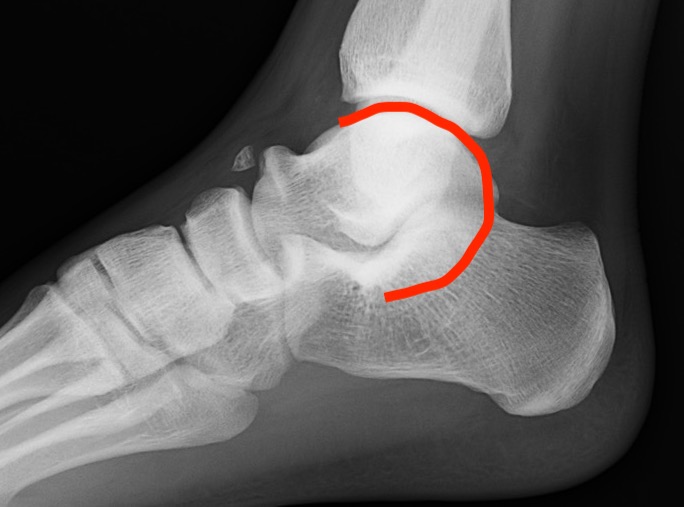

Xray

| Talar beaking | C Sign | Harris axial view | Ball and socket ankle joint |

|---|---|---|---|

| Traction spur due to increased stress | Medial outline talar dome and posterior sustenaculum tali |

40 degree axial view Ski jump view Visualize middle facet |

Secondary to rigid subtalar joint Develops to allow inversion / eversion |

Talar beaking with C sign